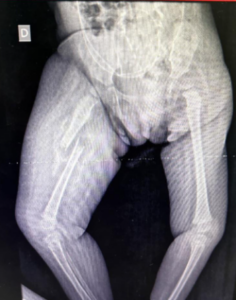

Radiogafia de membros inferiores, evidência o seguinte achado:

Diante desse achado e da história clínica apresentada, qual das seguintes características da história clínica levanta suspeita de maus-tratos?

DHistória inconsistente com o tipo de lesão observada